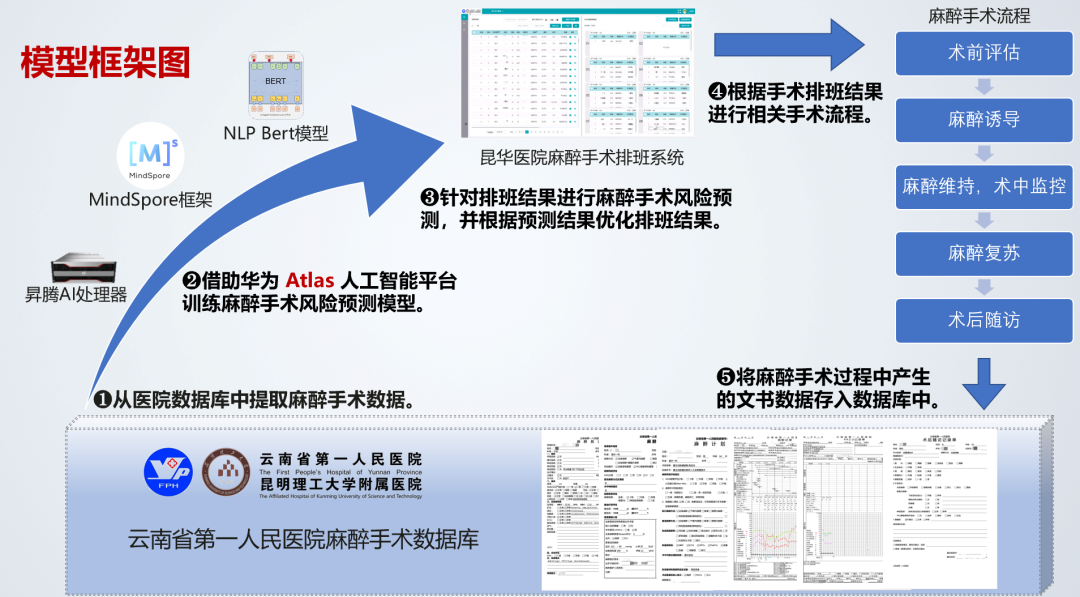

云南联合视觉基于昆明市人工智能计算中心充沛算力底座,以及昇思MindSpore全场景AI框架,训练麻醉手术风险预测NLP Bert模型,利用术前的患者访视信息和麻醉医生信息进行术中麻醉风险和术后麻醉并发症的预测,并将预测结果作为医患匹配度的衡量标准。综合考虑手术、麻醉和患者因素,通过对于麻醉风险进行预测,合理分配有限的医疗资源,做好麻醉预案,降低麻醉和手术的风险,保障患者的生命安全。

(麻醉手术风险预测”联合解决方案模型框架图)

麻醉手术风险预测联合解决方案实现对手术麻醉全过程的闭环管理。该方案减轻了麻醉医生工作压力,协助麻醉医生完成术前评估和术后随访工作,制定更加科学的麻醉方案。同时该方案实现手术申请、手术麻醉安排、术中物资清点等业务的计算机管理,将工作人员从繁重的手工记录、统计中解脱出来。